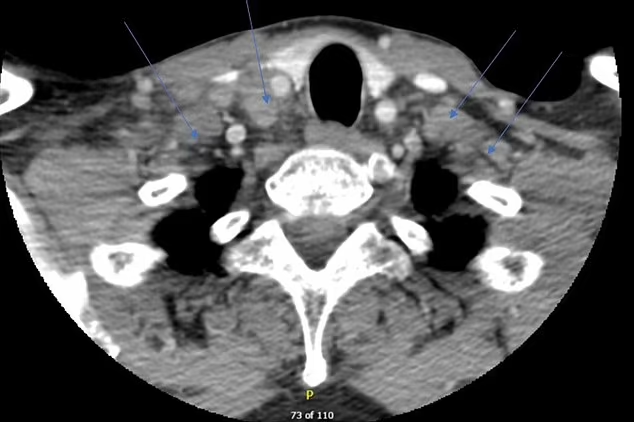

The 47-year-old patient, who was living in India, had a latent TB infection with no symptoms. Five days after receiving a Covid booster shot, he developed intense flu-like symptoms, including fever, exhaustion, and night sweats.

Doctors determined that the vaccine had strongly stimulated his immune system. Instead of responding in a balanced way, his body launched an aggressive inflammatory attack against the hidden TB bacteria. This reaction led to a condition known as tuberculosis immune reconstitution inflammatory syndrome, or TB-IRIS. Researchers say this is the first documented case linked to a Covid booster.

The patient’s medical history was complex. He had recently been diagnosed with rheumatoid arthritis and was taking immune-suppressing medication. After TB was identified and treated, his symptoms initially improved. However, they returned more severely following a third Covid dose.